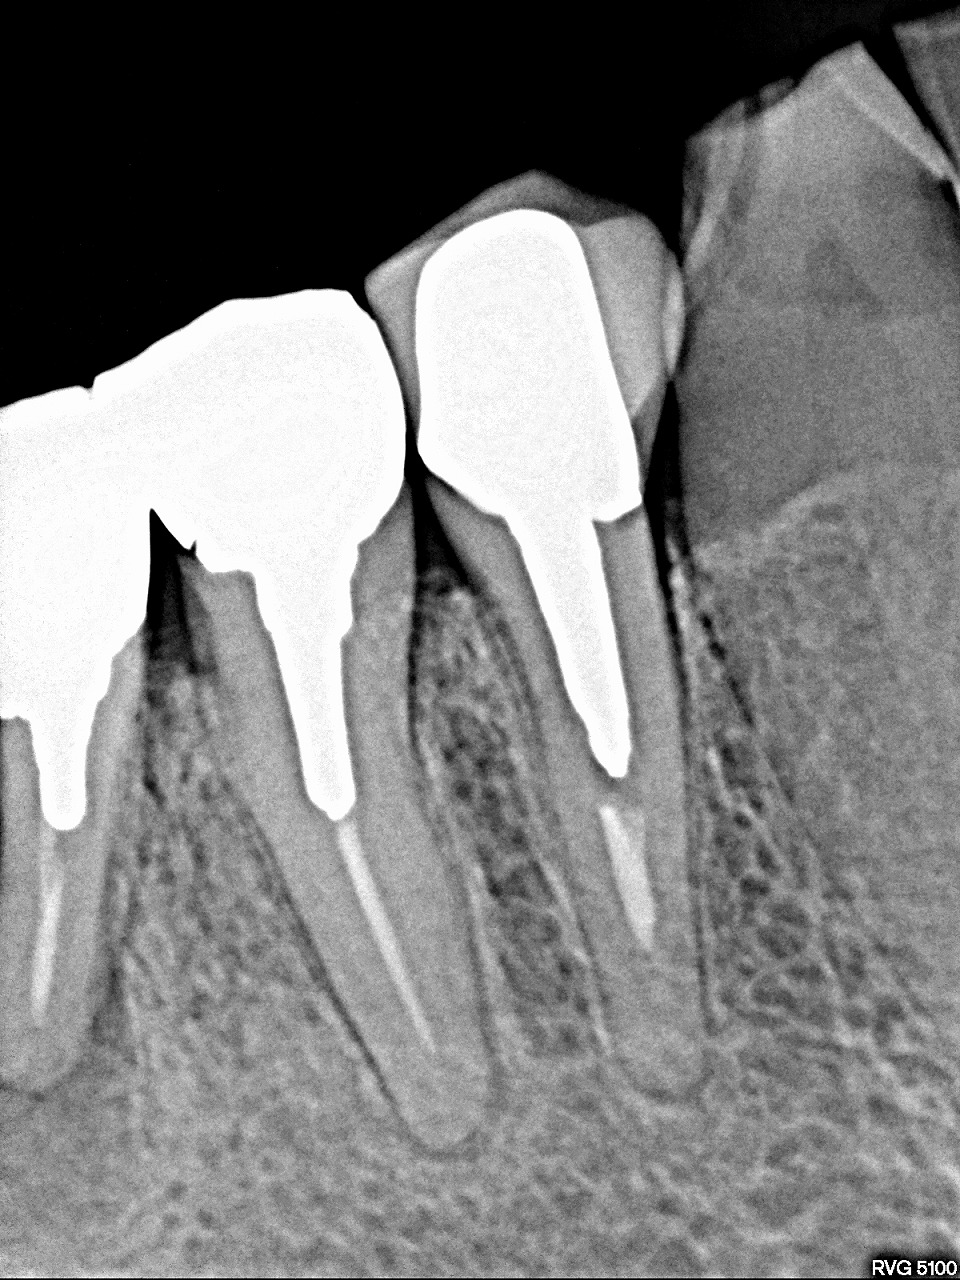

右下インプラント埋入 2本埋入 早期埋入|お知らせ |広島市安佐南区の歯科医院 右下インプラント埋入 2本埋入 早期埋入 トップ お知らせ・ブログ お知らせ 右下インプラント埋入 2本埋入 早期埋入 右下インプラント埋入 2本埋入 早期埋入 右下が腫れて痛んできました レントゲンです 分割してある歯の根尖病巣が見られます クラウンを外しました 切開して海を出すとともに補綴を外していきました 抜歯させていただき、数か月待ちました 埋入時になります かなり穴は開いています 補填材を詰めていき、縫合して埋入が終了になります Web診療予約 初めての方へ 選ばれ続ける理由 院内設備について 歯が痛いしみる一般歯科 歯がぐらぐらする歯周病 健康な歯を保ちたい予防歯科 子供の虫歯予防をしたい小児歯科 銀歯をセラミックに審美歯科 白い歯を目指しませんか?ホワイトニング 矯正専門医がいるので安心矯正歯科 抜けた歯を補いたいインプラント・入れ歯 医院案内 スタッフ紹介 メリィハウス歯科クリニックオフィシャルホームページ ラベンダー歯科クリニックオフィシャルホームページ お知らせ・ブログ ホーム 診療科目 一般歯科 歯周病治療 予防治療 小児歯科 審美治療 ホワイトニング 矯正歯科 入れ歯・インプラント マウスピース矯正 初めての方へ 院長・スタッフ 設備紹介 医院案内・アクセス メニューを閉じる